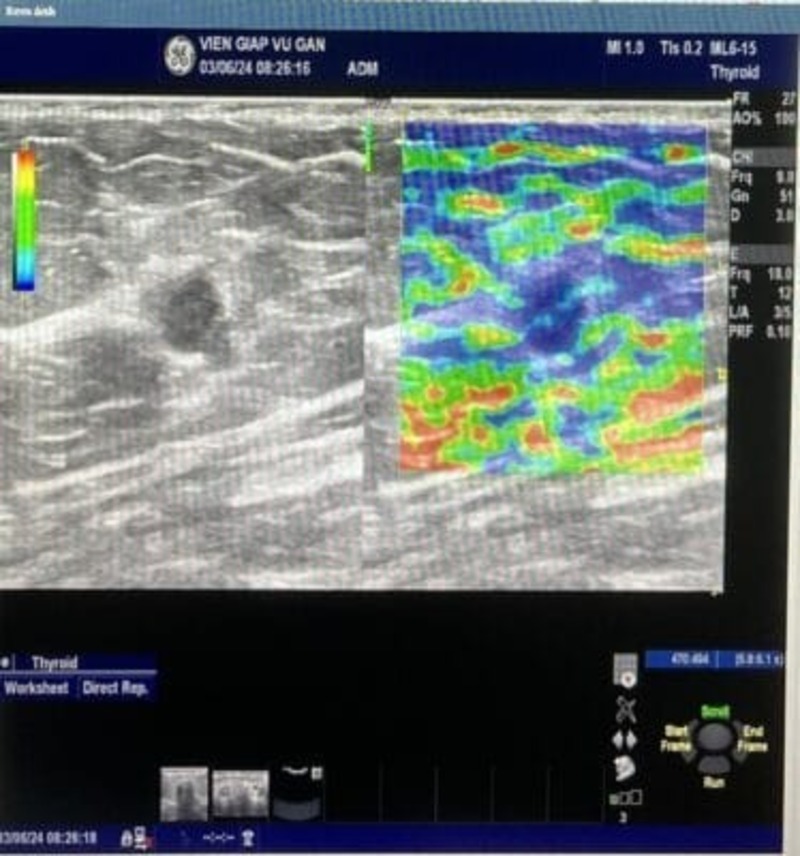

SIÊU ÂM: Vú trái vị trí 2g rìa vú ghi nhận 1 khối echo kém, bờ đa cung nhỏ, có chỗ tạo góc, trục ngang, mạch máu phân bố thẳng góc vào bên trong.

Hạch nách trái không ghi nhận hạch bệnh lý.

Kết luận: Tổn thương vú trái BI-RADS 4A